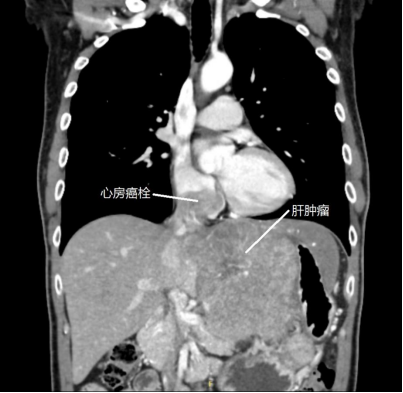

结果CT报告显示,黄先生的肝脏几乎被一个巨大型肿瘤覆盖住,而且已经有出血症状,肝中静脉癌栓,门脉右支、肝右静脉远端受侵犯,肝硬化并发门脉高压症、胃底及胃网膜静脉曲张,已是晚期肝癌的表现。

“特别棘手的是,这位患者的肝癌合并出血,如同生长在身体里的‘不定时炸弹’,如果处置不当,随时可能危及生命。”汪国营教授建议黄先生尽快入院治疗。